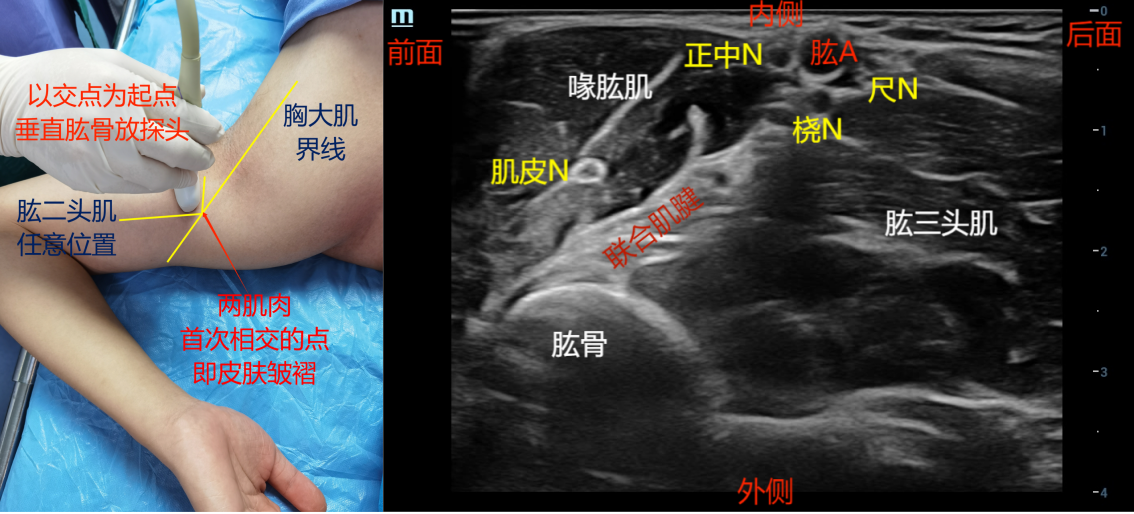

步骤是:首先将探头一端放在腋窝前壁胸大肌与肱二头肌首次相交点(近似相交也可以),探头长轴垂直肱骨放置(量皮肤皱褶连线上)。然后探头向后平移,向上、向下侧动或平移探头,确定腋动脉。然后追踪背阔肌和大圆肌,寻找到这2块肌肉汇合到肱骨上组成的联合肌腱(长条形较宽的高回声)这个解剖结构。再向上、向下来回侧动探头(探头尖端不动,探头尾部线缆向下、向上),观察联合肌腱的消失和出现,联合肌腱显示清楚就是腋窝臂丛阻滞的标准切面,因为该处桡神经正好位于腋动脉周围,再往下桡神经就远离肱动脉进入桡神经沟。

腋动脉:腋动脉前面偏外上方是正中神经,一般为低回声。腋动脉深面偏外侧为桡神经(联合肌腱的表面)。腋动脉的后面偏内侧为尺神经。

腋动脉的外侧两条肌肉影是肱二头肌和喙肱肌。

肌皮神经走行在这两块肌肉之间的筋膜间隙内,可往上移动探头,能观察到肌皮神经汇合到外侧束。

该图主要观察臂丛主要分支横断面上正中神经、尺神经和桡神经的横断面上的相对位置和联合肌腱前面观

该图主要观察皮肤皱褶的肌肉和联合肌腱的解剖